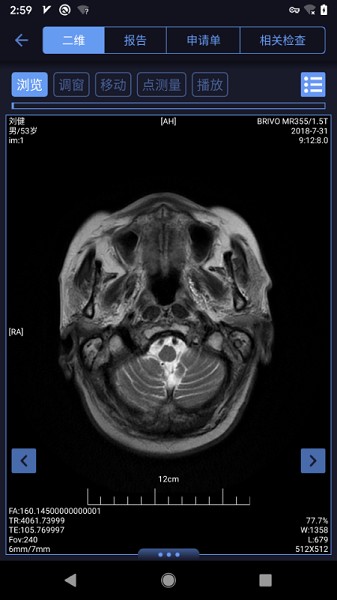

гІгУНиЭМ / Preview Picture